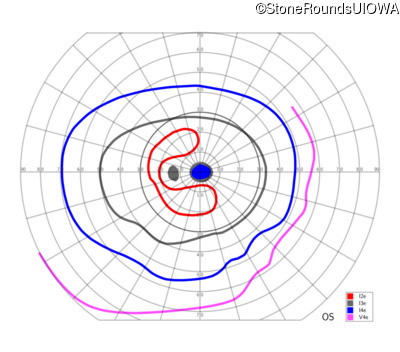

This 52 year old man had normal vision until his mid 30's when he began to have trouble distinguishing colors. the issuing 10 years he had a gradual loss of visual acuity accompanied by increasing photophobia.

| Age at visit: 55 years |

| Age at visit: 58 years |

| Age at visit: 61 years |

| Age at visit: 64 years |